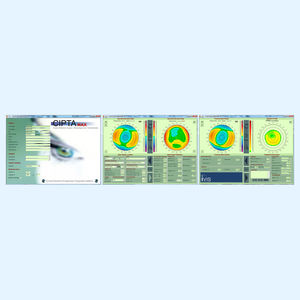

... Aplicando más de 2 décadas de Experiencia en Cirugía Corneal Personalizada. El software de planificación avanzada CIPTA® nació en 1996 para planificar tratamientos refractivos y terapéuticos totalmente personalizados, ...

iVis Technologies